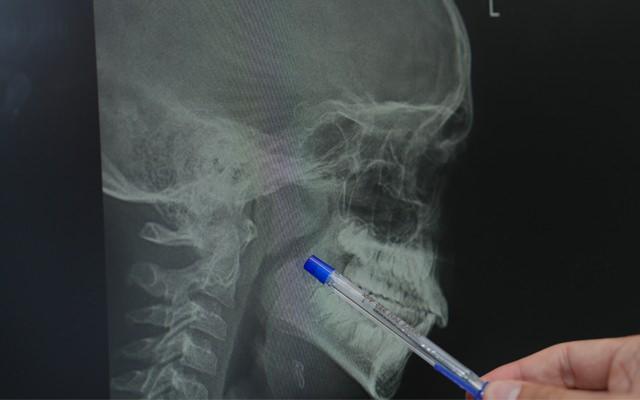

Dr. Çelik'e göre, eğer çocuğunuzun bademcikleri ve geniz eti solunum yolunu daraltarak uykuda nefes durmasına (apne), horlamaya veya sürekli ağız açık uyumaya neden oluyorsa, dikkat edilmesi gereklidir. Benzer şekilde, yıl içinde sık sık tekrarlayan ve antibiyotik tedavisi gerektiren bademcik enfeksiyonları da cerrahi bir müdahaleyi düşündürebilir.

Çocuklarda büyümüş bademcik ve geniz etinin sadece fiziksel değil, gelişimsel riskler de taşıdığını söyleyen Çelik, "Tedavi edilmediğinde büyüme ve gelişme geriliği, yüz yapısında bozulma, sık orta kulak enfeksiyonu ve okul başarısında düşüş gibi sonuçlarla karşılaşabiliyoruz" uyarısında bulundu. Her bademcik sorununun bademciğin tamamen alınmasıyla sonuçlanmayacağını dile getiren Dr. Çelik, "Eğer hastamız sık bademcik enfeksiyonu geçirmiyorsa ve sadece hava yolu tıkanıklığı varsa bademcik küçültme işlemiyle sorun çözülebilir" dedi.

Ameliyat tekniklerine de değinen Dr. Çelik, geniz eti operasyonlarının klasik veya buharlaştırma yöntemiyle yapılabildiğini belirtti. Bademcik ameliyatlarında ise sıcak ve soğuk yöntemler kullanıldığını söyledi.